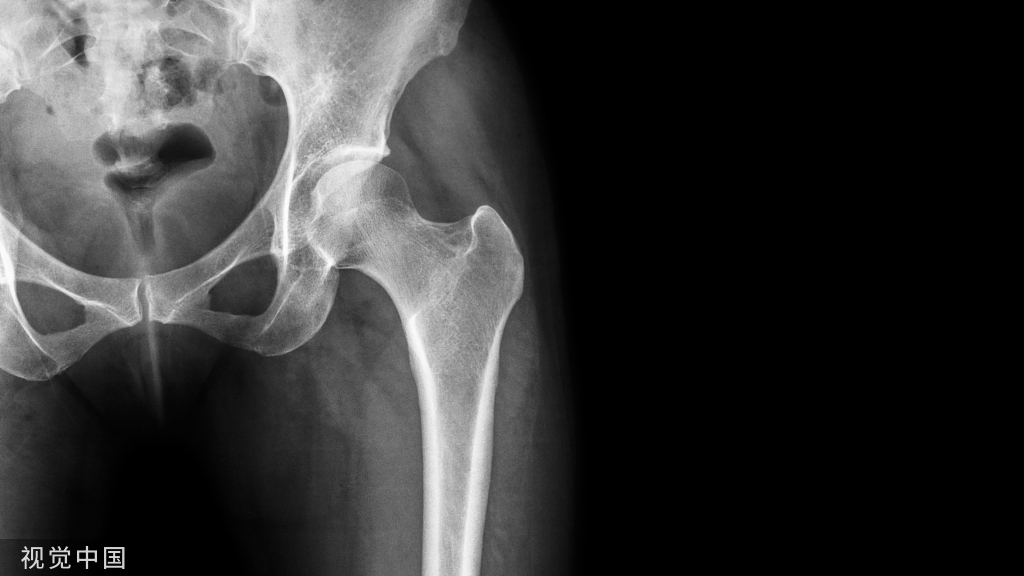

髋关节镜手术切口多大,是否微创,

是否影响美观?术后疼痛如何?

髋关节镜技术是一种微创手术技术,2-3个长约1cm(小指宽度)的微小切口,比传统大切口开放手术的创伤要小很多需要,术后疼痛更轻(仅需要口服少量止痛药即可),1-2周疼痛明显减轻,康复更快(2-3天拄拐下床活动)。